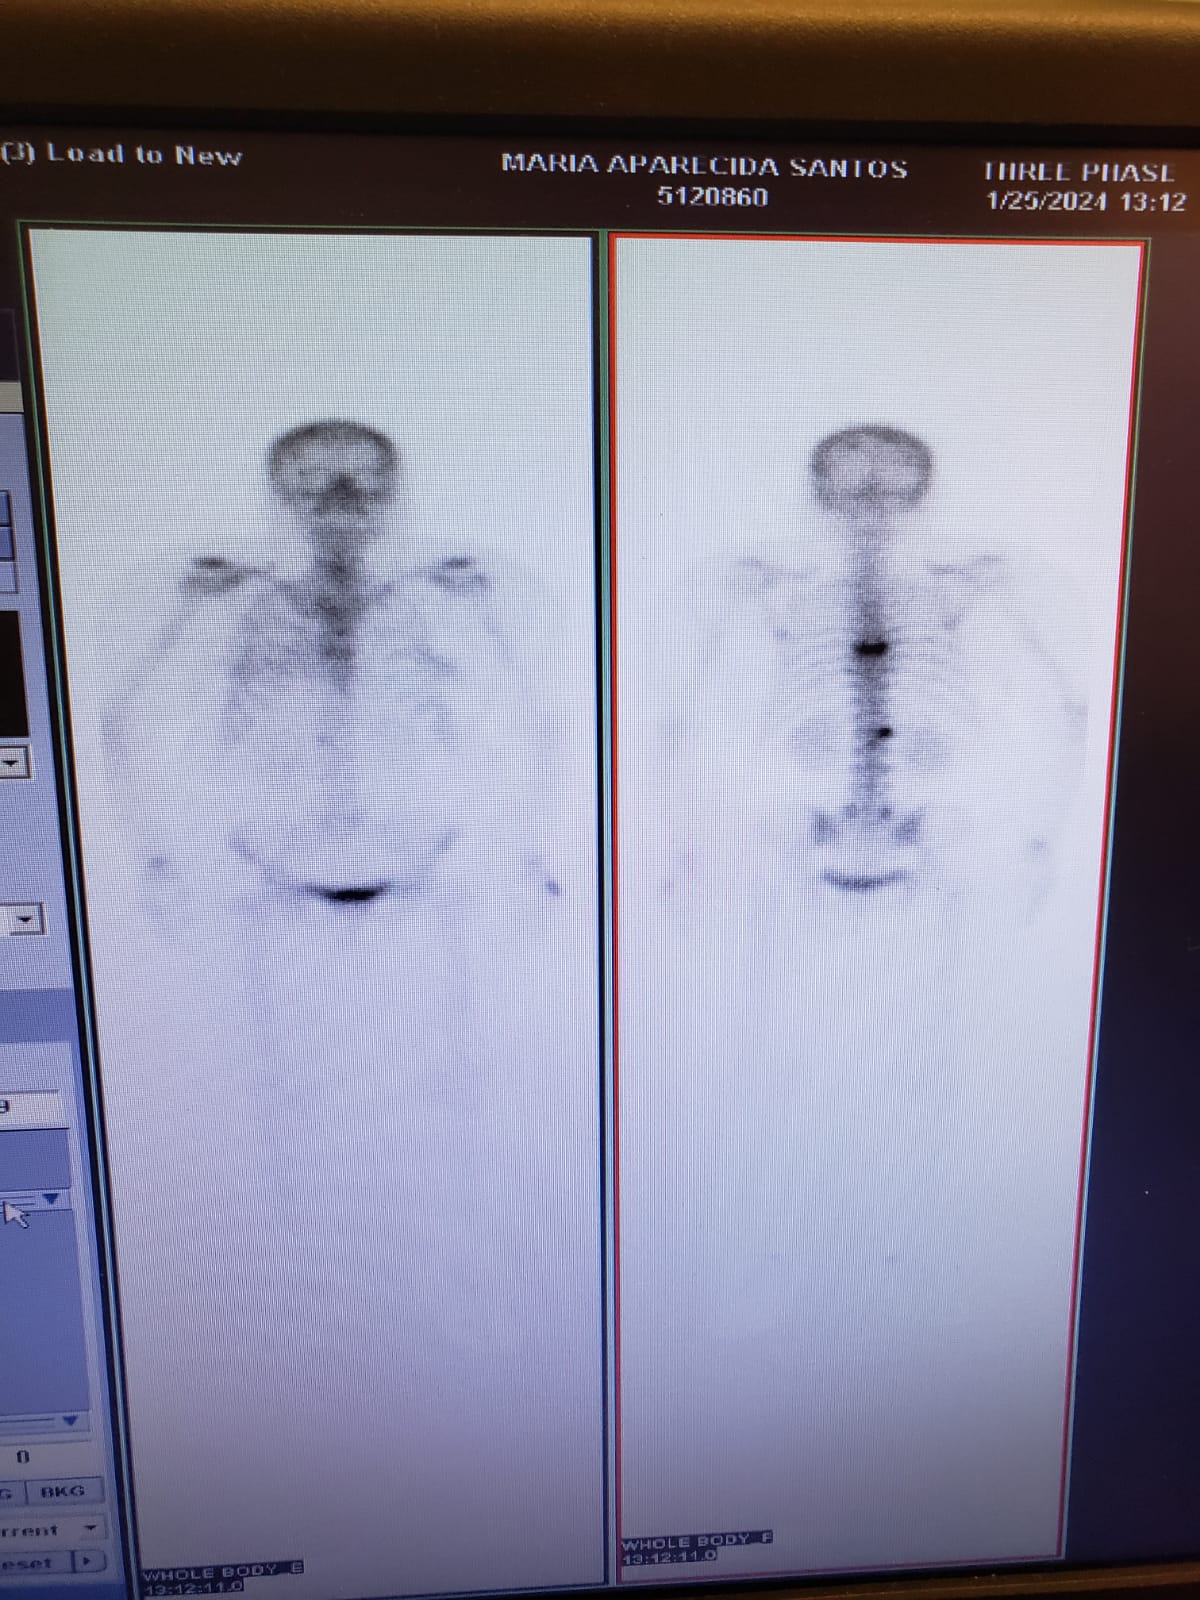

me chamo felipe, tenho 31 anos, trabalho na trabalho na área da saúde como cuidador no brasil, sou técnico de raio x e estudante de biomedicina no brasil